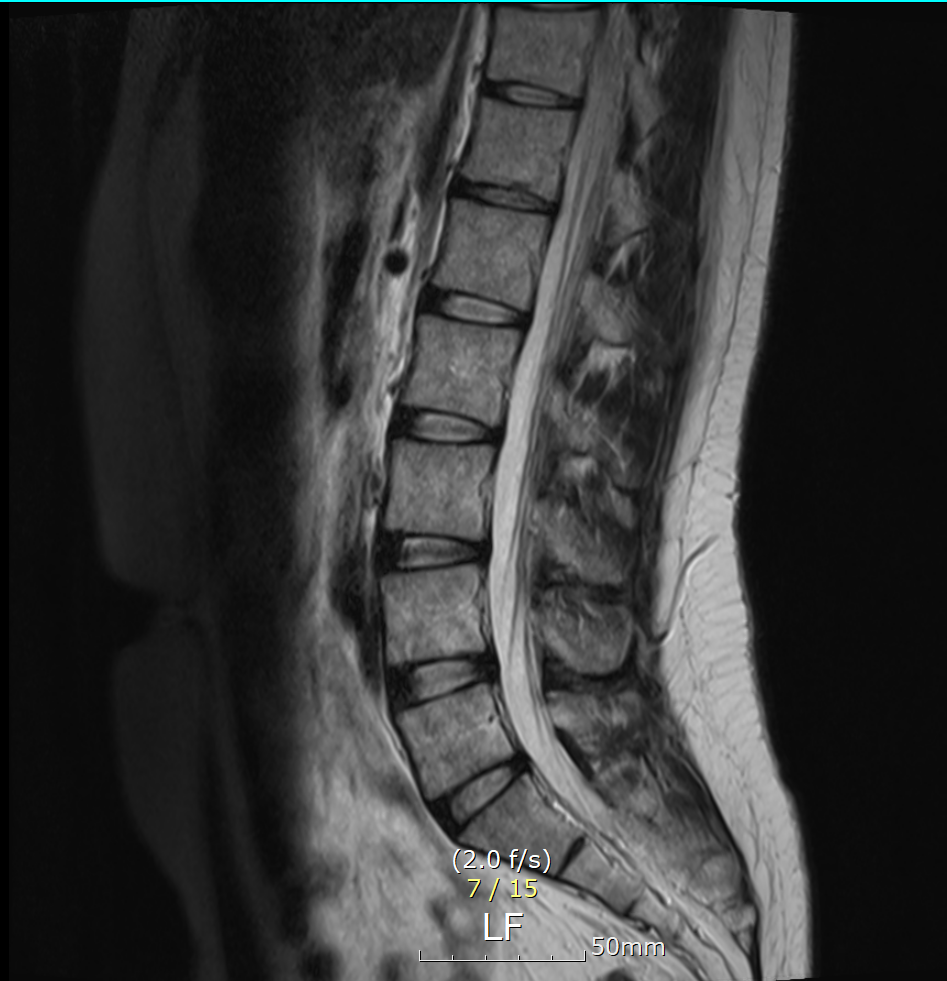

T12-L1 level에서 disc가 뒤쪽 Lt. central aspect로 protrusion되어 있고 mild한 dural sac indentation을 주고 있음.

그 외 disc level과 neural foramen에서 definite한 abnormality는 보이지 않음.

Vertebral body의 SI, shape, 그리고 alignment도 정상이며, scanned TL-spinal cord내에 definite한 abnormal signal intensity는 보이지 않음.

아래 사진에 있는 부위가 아마 T12/L1 사이에 디스크가 살짝 뒤로 빠져있다는 부위이실겁니다.

옆에서 보면 두번째 사진이구요.

우선은 이 디스크 내장증으로 인한 연관통으로 보고 요추전만 자세를 잘 실천해보시는게 가장 우선 필요한 조치이겠습니다.

수술을 주로 다루는 신경외과, 정형외과 선생님들의 경우에 심한 디스크탈출 및 신경뿌리를 누르는 신경뿌리병증이 생길만한 병변만 통증을 유발한다고 보시기 때문에 문제될만한 병변이 없다고 이야기 하셨을텐데 저렇게 작게 찢어진 디스크 때문에도 충분히 통증이 생길 수 있습니다. 물론 찢어진 디스크의 위치에 비해 통증이 밑에 있는 편이시지만 이게 불가능한건 아닙니다. 디스크 내장증이라고 하며 이럴때는 요추전만 자세가 가장 중요합니다.